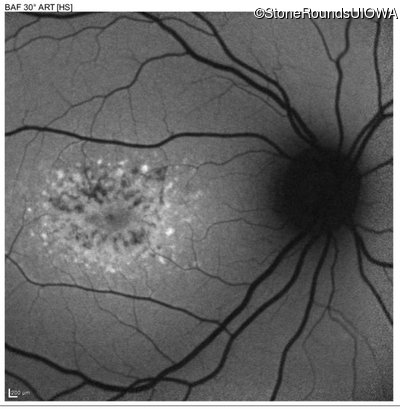

| Age at visit: 22 years |

| Disease | Gene | Allele 1 variant(s) | Allele 2 variant(s) | Inheritance mode |

|---|---|---|---|---|

| AR Stargardt Disease | ABCA4 | Asp507Tyr GAT>TAT | IVS40+5 G>A | AR |